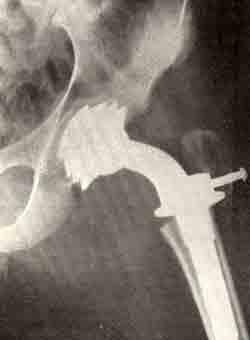

В клинике детской костной патологии и подростковой ортопедии ЦИТО проведено 30 оперативных вмешательств 22 больным: надмыщелковая остеотомия по Репке (4 операции), перемещение надколенника по Ру — Фридланду — Волкову (10 операций), артропластика тазобедренных суставов (2 операции), подвертельная остеотомия (одна операция), корригирующая остеотомия костей голени (4 операции), артропластика тазобедренного сустава по Сивашу (2 операции), миотомии.

Хирургические вмешательства производились уже как восстановительные (атропластика с использованием амниотических и фасциальиых колпачков, замена сустава аллопластическим). Результаты артропластики тканями хуже, чем аллопластики.